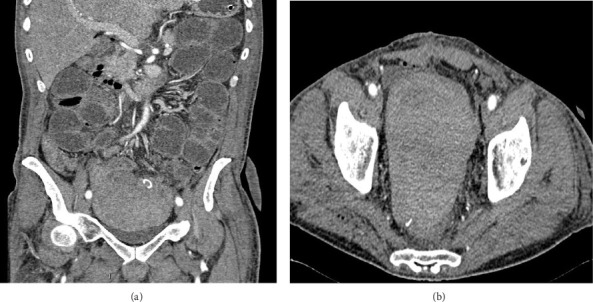

获得性凝血因子XI (FXI)抑制剂是出血性疾病的罕见病因,通常与自身免疫性疾病或恶性肿瘤相关。虽然不常见,但这些抑制剂可导致严重出血,这可能难以控制。获得性FXI抑制剂与恶性肿瘤相关的病例报道数量有限。本病例报告一例罕见的获得性凝血FXI抑制剂发生于60岁男性乙状结肠腺癌患者。患者经历了严重的息肉切除术后消化道出血,并在实验室检查显示活化部分凝血活素时间(aPTT)延长和因子IX、XI和XII活性降低后被诊断为FXI抑制剂。病人接受了手术,并出现了危及生命的失血性休克。他再次手术,并开始使用重组VIIa因子(rFVIIa)、氨甲环酸和口服皮质类固醇治疗。治疗成功地控制了出血,消除了抑制剂。该病例强调了获得性FXI抑制剂患者严重出血的风险,并强调了早期诊断和个性化治疗的重要性。由于复发的风险,特别是与恶性肿瘤相关的病例,定期监测是必不可少的。